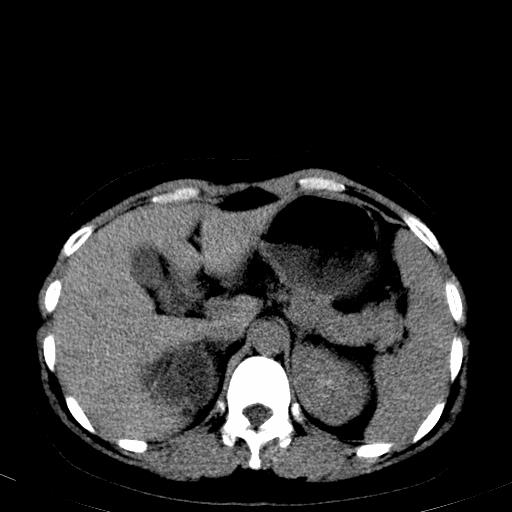

右肾多发囊肿,左肾、左输尿管结石

左肾不像是结石吧,是不是做过造影啊

左肾哪里有结石???

第一个序列应该是延迟图像吧;

左肾不是结石,是造影后改变.右肾积水,功能仅存.